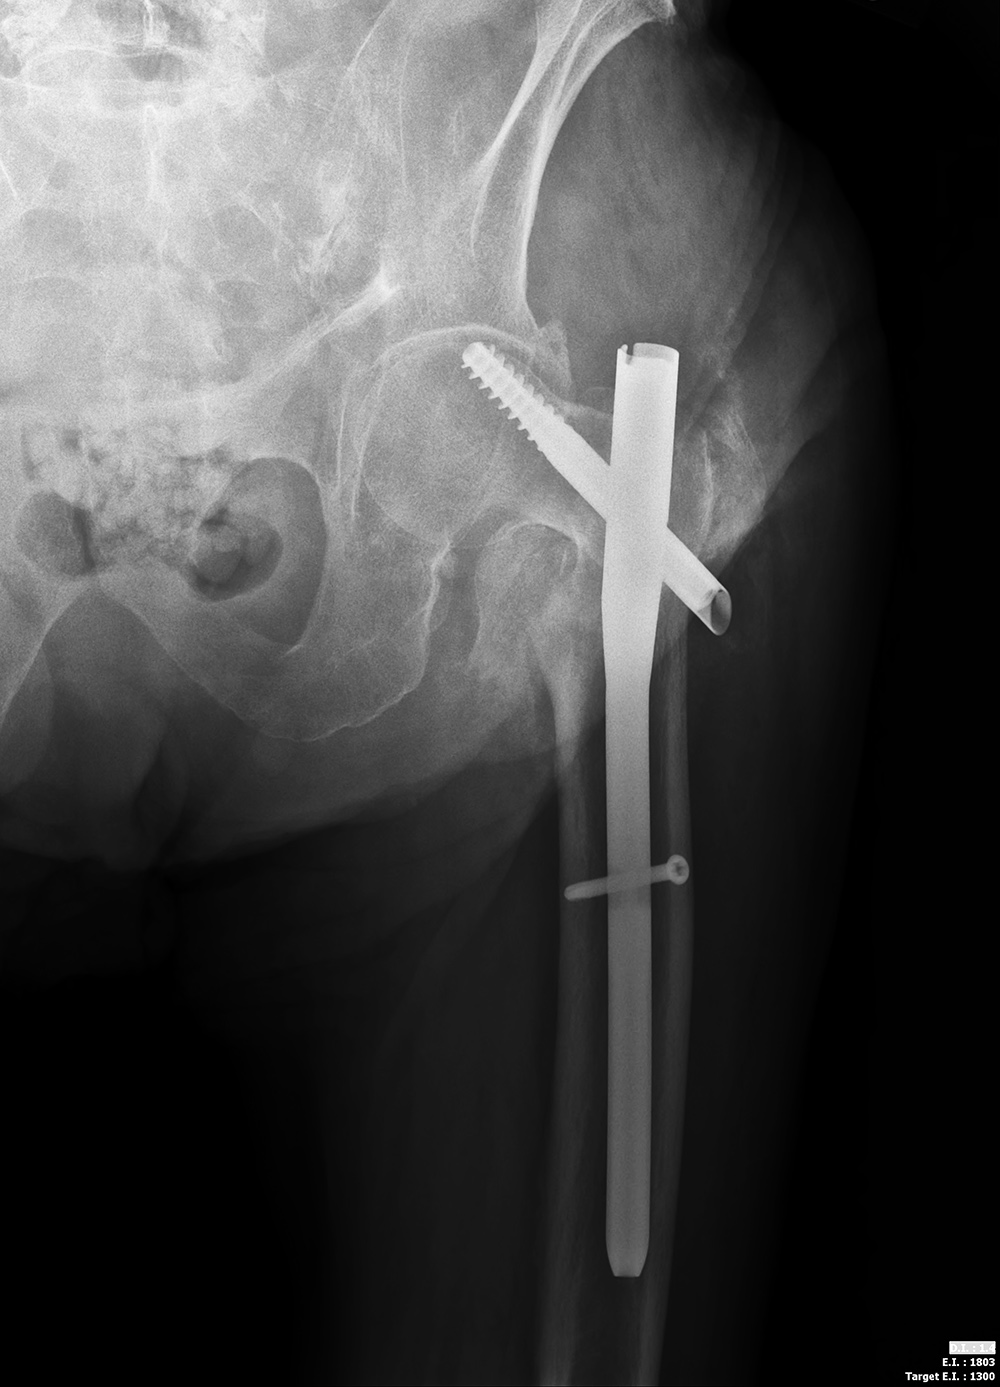

| The compression screw has slid distally in the barrel as it was designed to do when the femoral neck fracture site becomes compressed. This did not prevent the screw from cutting out of the femoral head (curved arrow). From Hunter, 1994 |